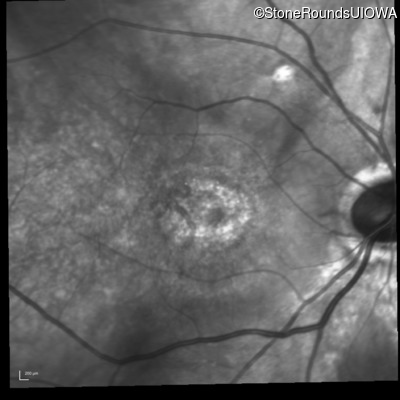

Infrared Fundus Photograph - Right - 20/125 -2

Exemplar